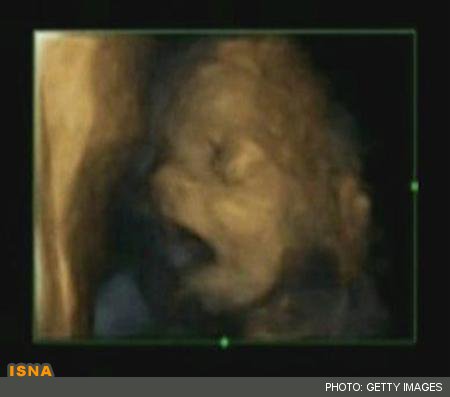

خمیازه کشیدن جنین در رحم (+عکس)

در حالی که برخی از دانشمندان پیش از این از این عمل جنین در رحم خبر داده بودند،‌ برخی دیگر این موضوع را رد کرده و آن را تنها یکی از رفتارهای کودک در حال شکل گیری و باز و بسته کردن دهان خوانده بودند.

اما محققان انگلیسی در پژوهش خود که در مجله PLOS ONE منتشر شده، به قطعیت اظهار کرده‌اند که توانسته‌اند عمل خمیازه را از باز و بسته کردن عادی دهان بر مبنای زمان باز بودن آن، کاملا تشخیص دهند.

پژوهشگران این کار را با استفاده از فیلم چهار بعدی برای بررسی تمام زمان‌هایی که جنین دهان خود را باز می‌کند، انجام دادند.

به گفته محققان، عملکرد و اهمیت خمیازه در جنین هنوز ناشناخته بوده اما این یافته‌ها نشان داده که شاید این عمل با رشد نوزاد ارتباط داشته و می‌تواند نشانگر سلامت جنین باشد.

آنها همچنین اظهار کردند که بر خلاف انسان بالغ، جنین به شکل مسری یا در اثر خواب‌آلودگی خمیازه نکشیده، بلکه تناوب آن در رحم ممکن است با بلوغ مغز در اوایل بارداری مرتبط باشد.

این پژوهش بر روی هشت جنین پسر و هفت جنین دختر از 24 تا 36 هفتگی بارداری انجام شد. محققان دریافتند که خمیازه کشیدن از 28 هفتگی کاهش یافته و هیچ تفاوت چشمگیری در تعداد خمیازه میان دختر و پسر وجود ندارد.